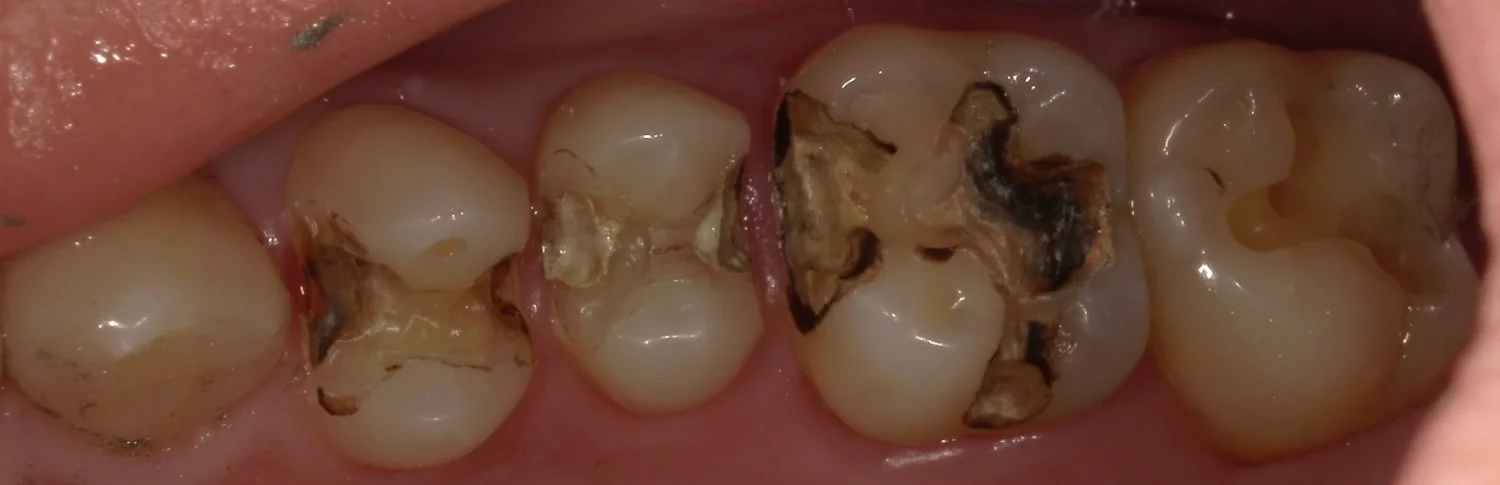

そして、金属と白い詰め物を外したのがこちら。

右から2番目については非常に真っ黒になっているのが分かりますね。